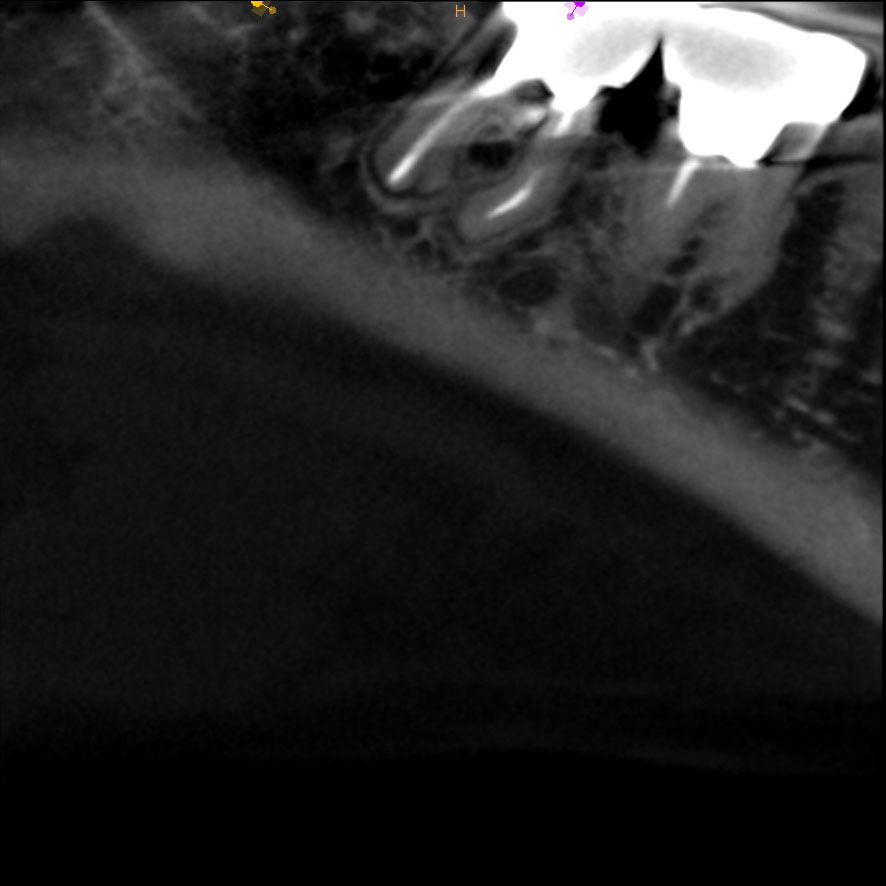

CT写真

11年後、当時の主訴であった右下一番奥(7番)の根っこの先の黒くなっている部分は白く改善されています。勿論、患者さんも不都合は訴えていません。しかし、顎骨内部の骨(海綿骨)の状態は一般的な歯科のレントゲンであるパノラマ、デンタルでは把握できないので、正確な情報を知りたい場合、歯科用CTによる精査が必要となります。

再歯内療法した左下6番の根の先は改善しているように見えます。(まだ数か月単位なので被曝量も考慮し、歯科用部分CT撮影は行っていません。)